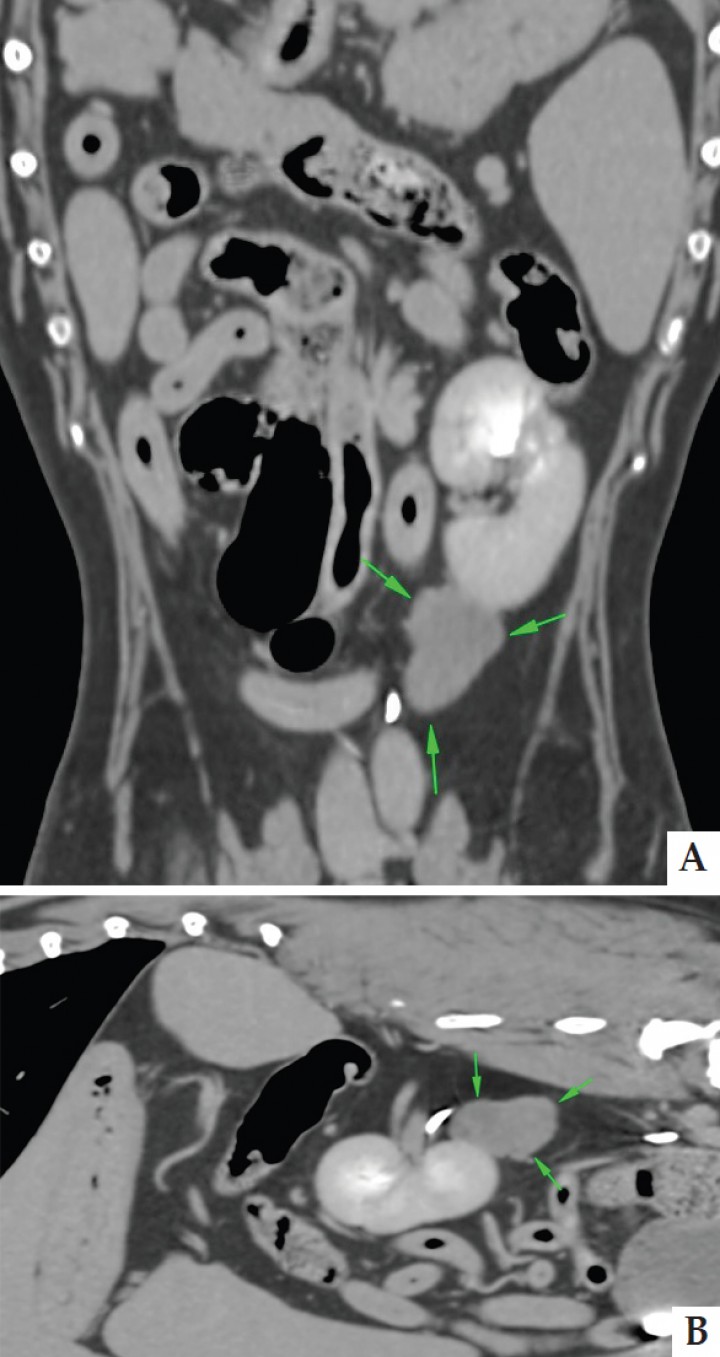

Se decidió realizar una tomografía computarizada (Toshiba Aquilion® 16 cortes, modelo CBTB-016A, 3-200V, 50/60Hz 1.2 KvA, California) de abdomen y tórax con contraste intravenoso (IV) iodado no iónico iomerol 400 mgl/kg (Iomeron® 250 mg/ml, s.p.a Milán). Este examen complementario se realizó para determinar la localización exacta de la masa y su relación con los tejidos circundantes, así como para descartar metástasis. Se observó una masa retroperitoneal izquierda localizada en íntimo contacto con el polo caudal del riñón izquierdo a nivel caudo-dorsal y medial. Esta masa irregular en su forma era avascular (Fig. 2). Entre la fase pre-contraste y las fases post-contraste arterial y venosa, no se encuentran diferencias de atenuación basadas en mediciones de unidades Hounsfield (entre 25-41 en las distintas partes de la masa). En la fase venosa se observó el uréter izquierdo relleno de contraste, justo dorsal a la masa, sin evidencias claras de adherencias. El resto del abdomen y el tórax no presentaron anomalías.

<p>Imágenes de tomografía computerizada post-contraste: A. Reconstrucción dorsal. B. Reconstrucción sagital en ventana de tejido blando en fase arterial, donde se observa la localización caudo-medial de la masa en contacto con el polo caudal del riñón izquierdo.</p>

Imágenes de tomografía computerizada post-contraste: A. Reconstrucción dorsal. B. Reconstrucción sagital en ventana de tejido blando en fase arterial, donde se observa la localización caudo-medial de la masa en contacto con el polo caudal del riñón izquierdo.

La imagen avanzada, como la tomografía computerizada y la resonancia magnética nuclear, han facilitado enormemente el trabajo de acercamiento inicial y estadificación tumoral, siendo actualmente indispensable en la tipificación tumoral, el grado de invasión local y la localización de metástasis hacia los nódulos linfáticos y metástasis distantes.[ Tobias KM, Johnson SA. Textbook of Veterinary Surgery: Small Animal. Saunders, Philadelphia. 2012. ] Recientes estudios tomográficos han remarcado la heterogenicidad pre y post contraste de estos tumores, además de la invasión local que los caracteriza, contrariamente al caso descrito en esta publicación. Los hemangiosarcomas, han mostrado en un 76% de los casos, un aumento en la captación de contraste focal. Este hallazgo es producido por acumulación de contraste en los canales vasculares de dichos tumores, al contrario de otros sarcomas de tejido blando.[ Fukuda S, Kobayashi T, Robertson ID, et al. Computed tomographic features of canine non parenchymal hemangiosarcoma. Vet Radiol Ultrasound 2014, 55: 374-379. [PubMed] ] En el caso descrito no se observó captación de contraste, ya que en el momento de la tomografía la masa se caracterizó como avascular.